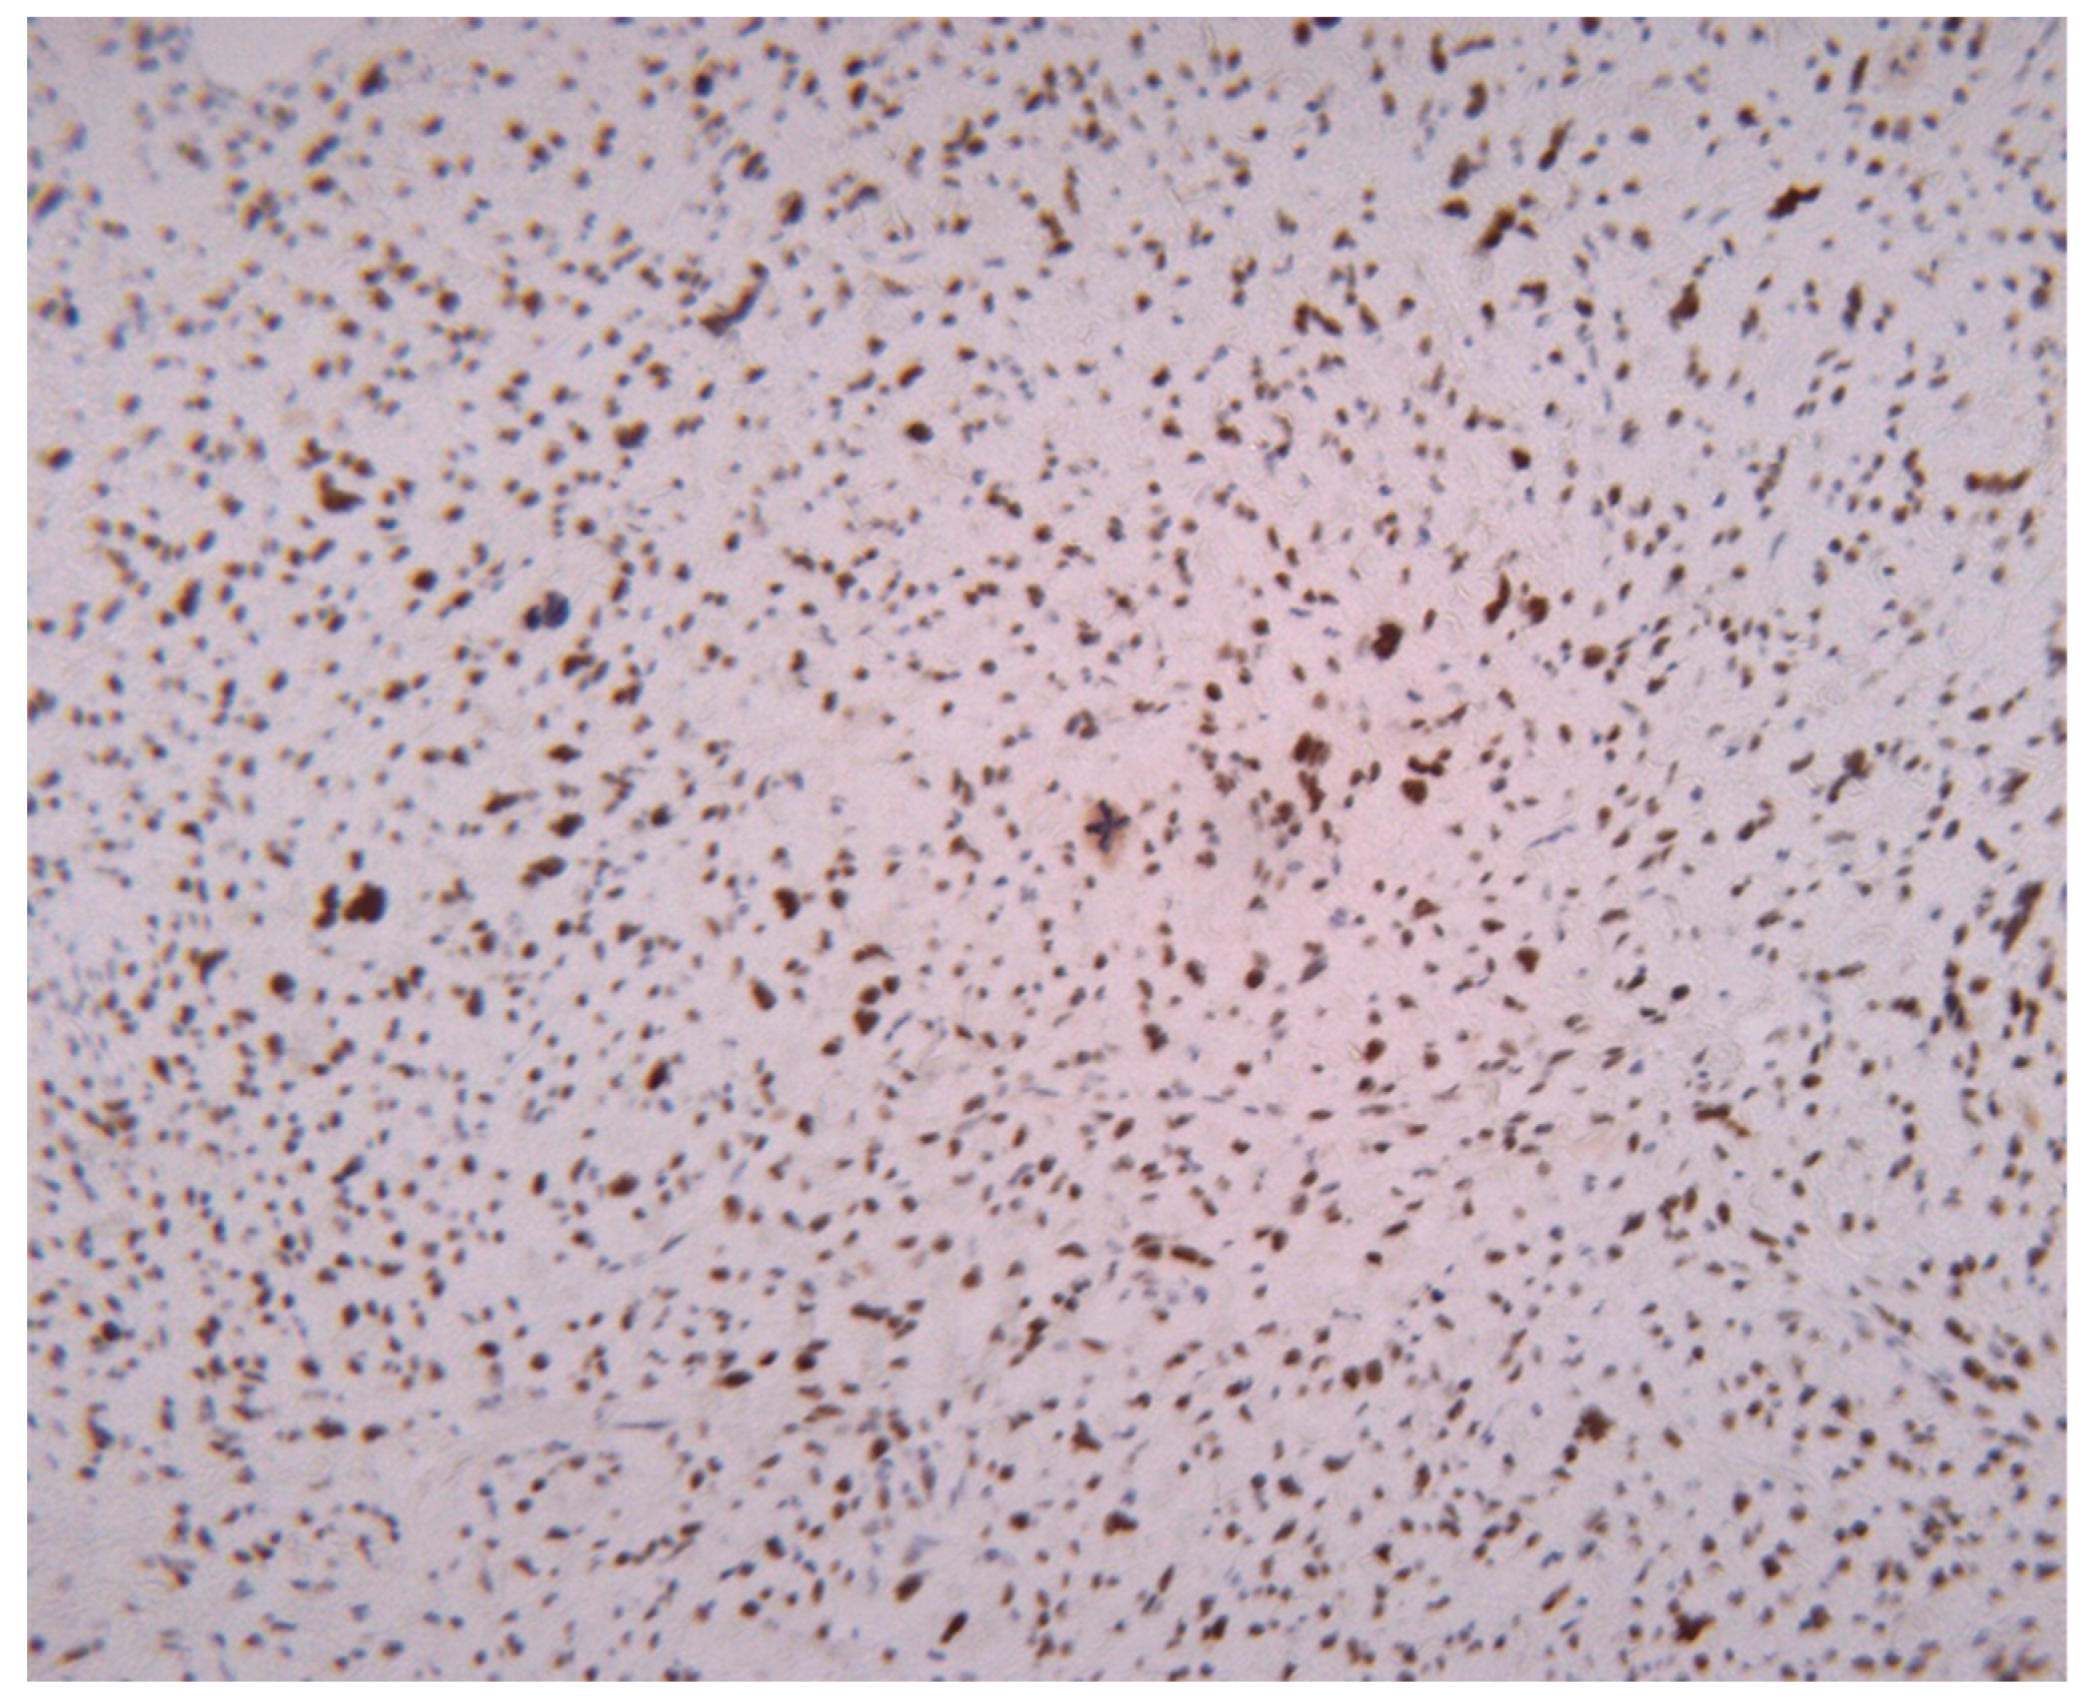

3.2. Proliferative Activity